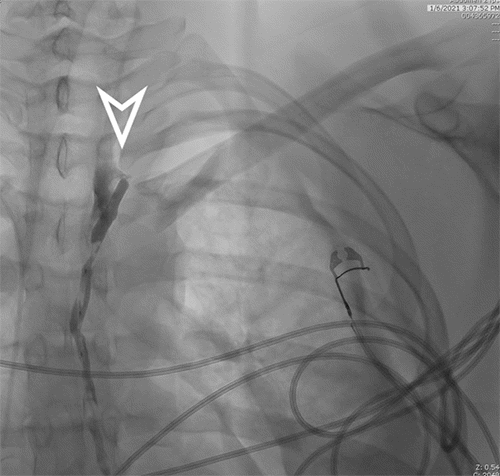

Interventional radiology performed a lymphangiogram to evaluate lymphatic drainage of the pelvic, abdominal, and thoracic regions. The study identified active extravasation from the thoracic duct near the clavicular head. The interventional radiologist then embolized the leaking segment using coils and glue (Figures 3-6). While chest tube drainage briefly declined, it returned to pre-procedure levels by postoperative day 2.

Figure 3. Early Filling of Cisterna Chyli over L1 (arrow). Published with Permission